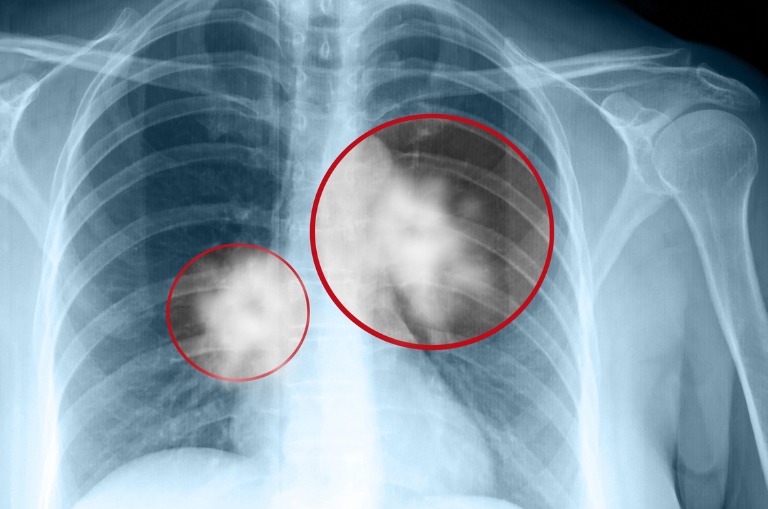

Was nach einer harmlosen Alternative zur Zigarette aussieht, kann langfristig ernsthafte Folgen für die Lunge haben: Neue Studien zeigen, dass bestimmte Aromastoffe in E-Zigaretten – sogenannten Vapes – die Atemwege reizen und bleibende Lungenschäden verursachen können. Das liegt daran, dass viele Vape-Liquids chemische Zusatzstoffe enthalten, die beim Erhitzen giftige Nebenprodukte bilden.

Diese gelangen durch Lungenzüge tief in die Lunge und können dort Entzündungen und strukturelle Veränderungen auslösen – auch bei jungen, zuvor gesunden Personen. Langzeitfolgen wie chronische Bronchitis oder eine eingeschränkte Lungenfunktion sind laut wissenschaftlicher Untersuchungen und Studien möglich.